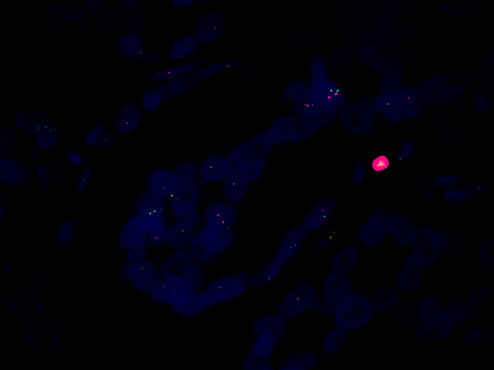

FISH荧光原位杂交是一种先进的显微镜技术,可以用于检测 HER-2 的表达水平。在癌症早筛中,荧光显微镜MF43-N可以用于对荧光染色的细胞进行观察,然后通过观察细胞中不同信号点的数量和分布来检测 HER-2 的表达水平。这种技术可以有效地检测出 HER-2 过度表达的细胞,为癌症的早期诊断提供重要依据。

总结起来,荧光显微镜MF43-N结合FISH荧光原位杂交技术观察 HER-2,是癌症早筛中的有效技术。通过使用这种技术,可以有效地检测出癌症的早期迹象,从而提高患者的生存率。